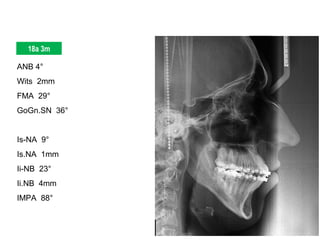

ANB 4°

Wits 2mm

FMA 29°

GoGn.SN 36°

Is-NA 9°

Is.NA 1mm

Ii-NB 23°

Ii.NB 4mm

IMPA 88°

Elementos de Diagnóstico

Perfil Mole Facial Convexo | Padrão Vertical | Nariz Proeminente

Assimetria Discreta | Linha do Sorriso Adequada

Classe I | Overbite | Mordida Cruzada Post-direita | Mordida Aberta 12/43

DM = - 10,2 mm Spee = -3 mm DC = - 1,6 mm IMPA 88°

18a 3m